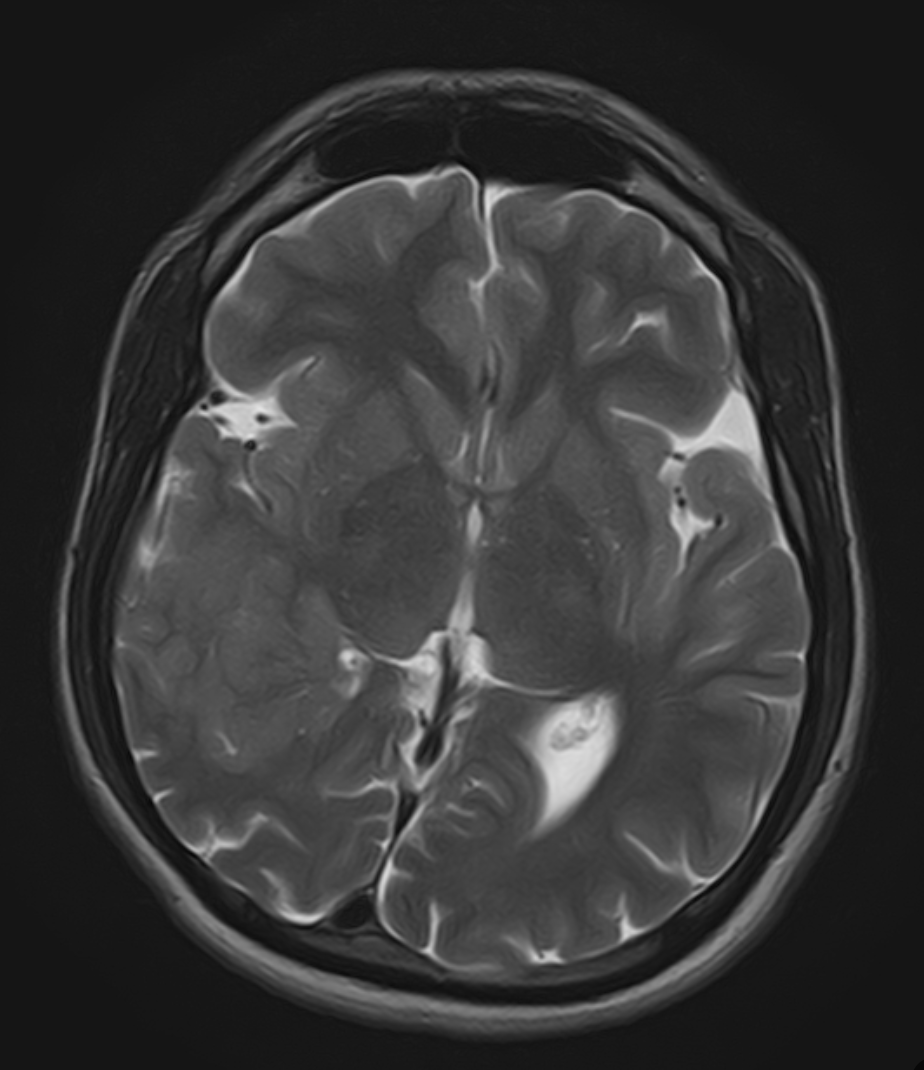

AI in daily radiology

Chest X-ray triage, fracture detection, mammography screening — studies flow from PACS, get processed, and results come back as DICOM Structured Reports and HL7 messages to RIS.